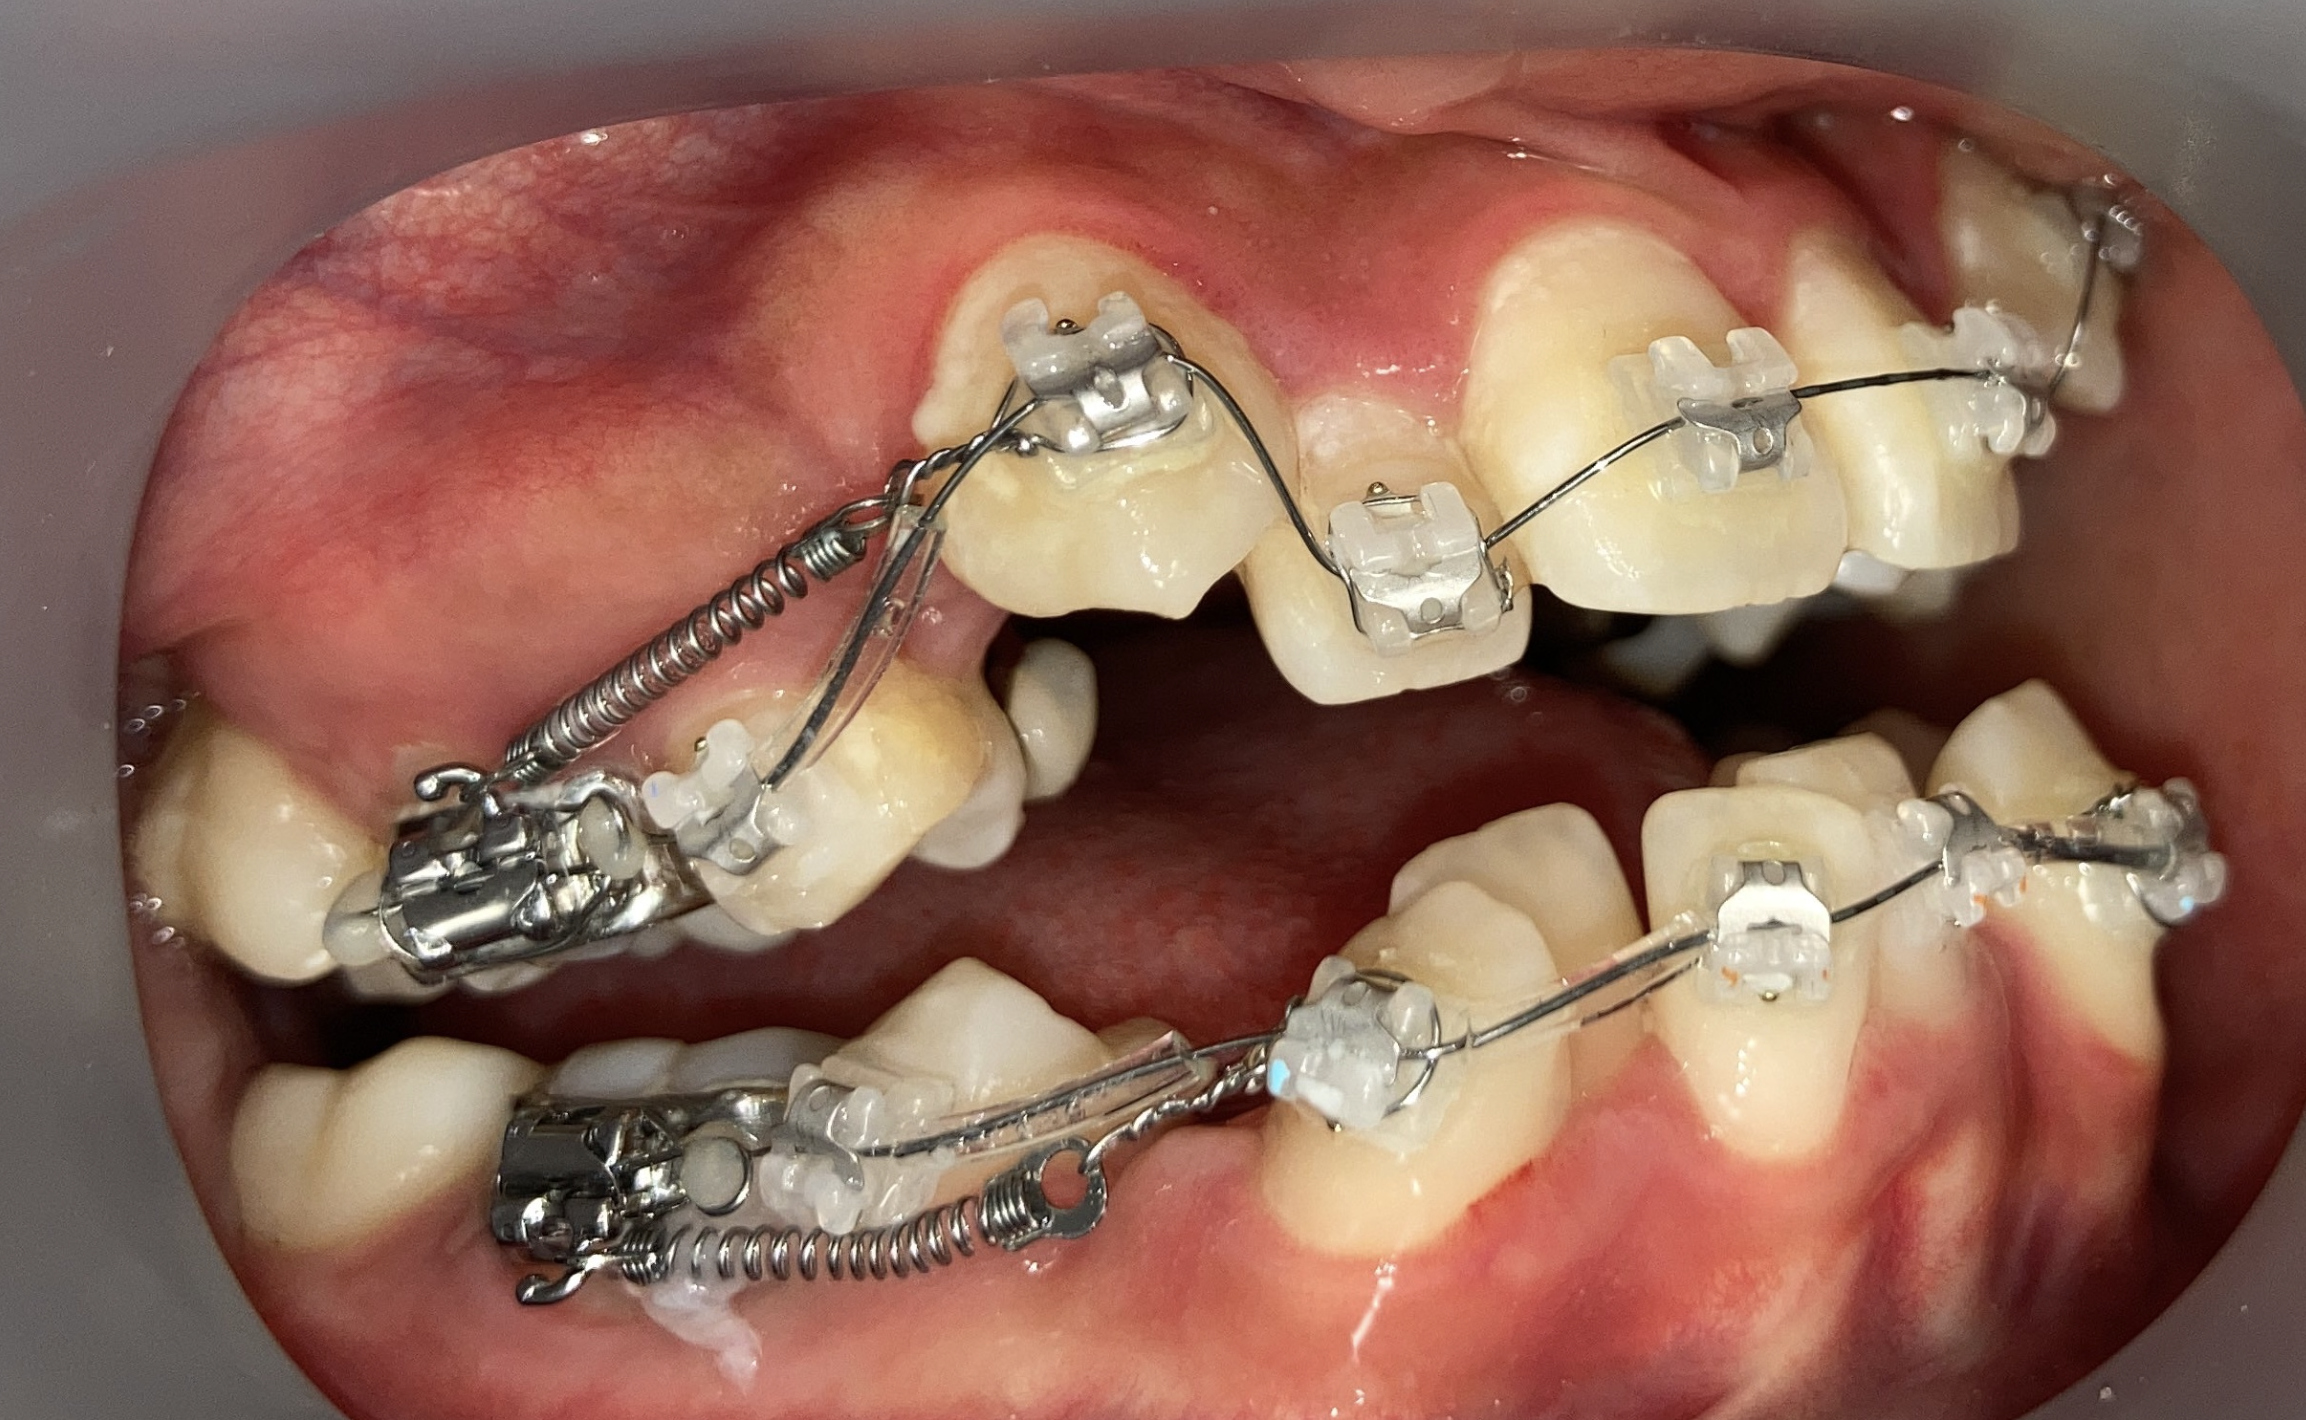

インプラントアンカー装着中の矯正治療経過|奈良の矯正歯科

アンカー装着中

インプラントアンカーで上の歯列全体を後方に移動。抜歯せずにガタガタと口元の突出感を改善しました。

ℹ️ ただし、この方法には限界があります。歯を後ろに動かせる量には上限があるため、口元の突出が大きい場合やガタガタが重度の場合は、非抜歯では対応できません。適応かどうかは精密検査で判断します。